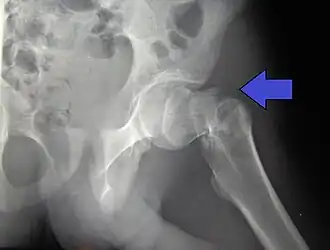

| Fratura intertrocantérica da anca em homem de 17 anos | |

| Tipos | Intracapsular, extracapsular (intertrocantérica, subtrocantérica, grande trocânter, pequeno trocânter)[1] |